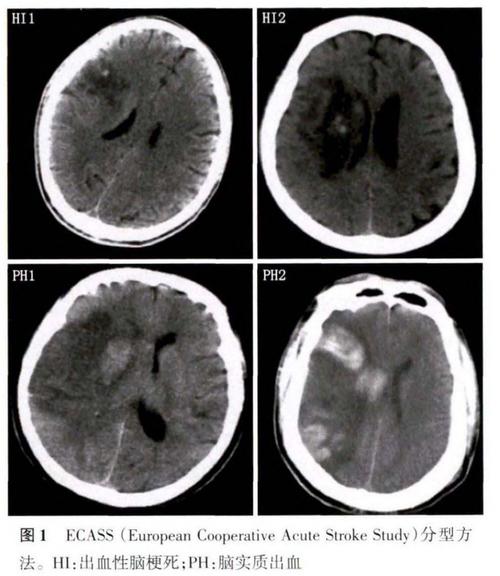

- 发病初期(超早期,0-6小时内): 脑血管堵塞后,脑组织细胞开始缺血、缺氧,但细胞结构尚未发生不可逆的破坏,脑组织的含水量变化极小,密度在CT上与正常脑组织几乎没有差别。这就是为什么CT显示正常。

- 发病后6-24小时: 随着缺血时间延长,脑细胞开始水肿,细胞结构被破坏,局部脑组织的水分含量增加,这时,在CT上才可能看到异常的低密度灶(暗区)。

- 发病24-48小时后: 水肿达到高峰,CT显示异常的清晰度最高,最容易诊断。

如果在发病后的数小时内做CT检查,尤其是在“黄金抢救时间窗”(发病后4.5小时内)内,CT有很高的概率是正常的,但这恰恰是最需要紧急干预的时期。